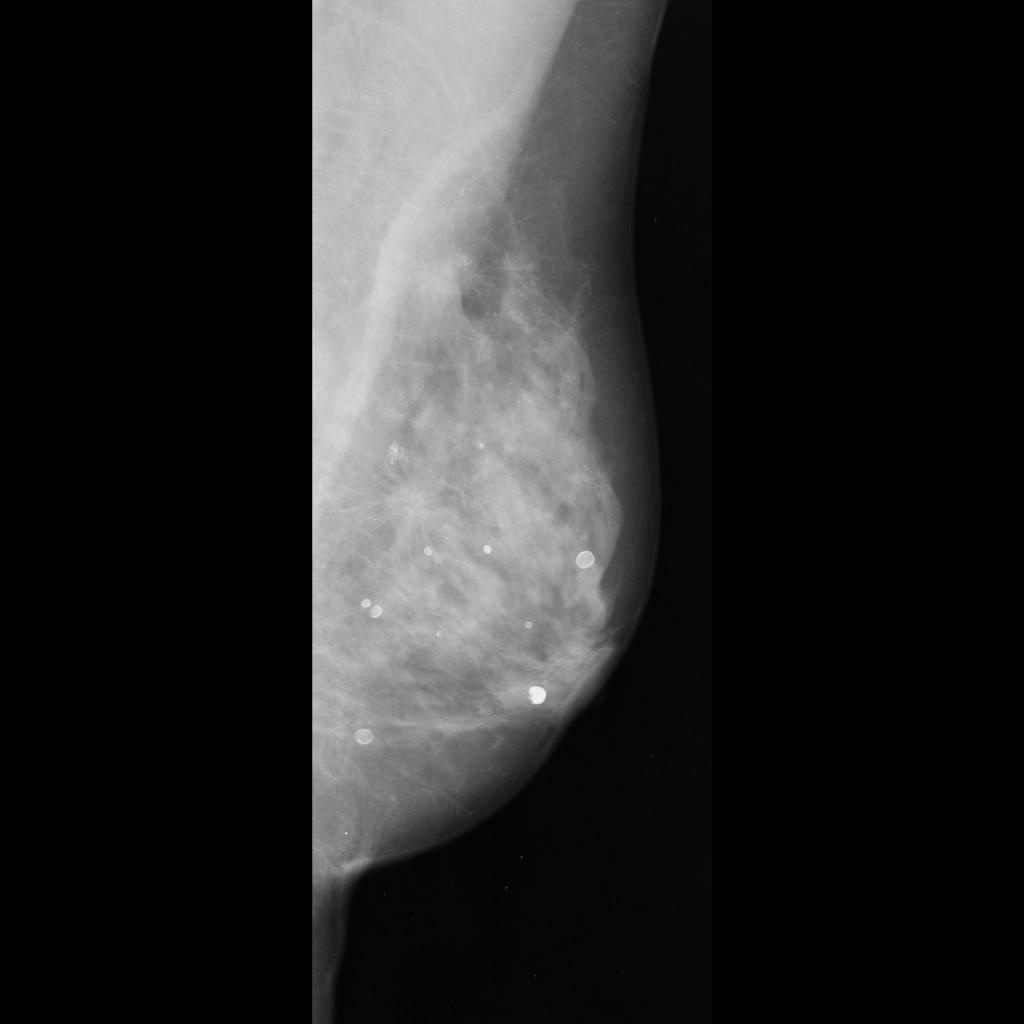

malignant